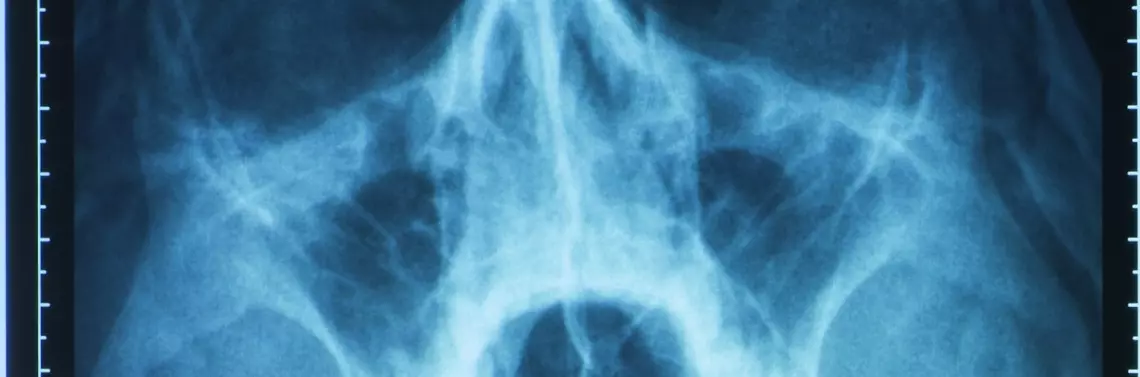

Zdj. 1. Umiejscowienie zatok

Tomografia komputerowa zatok

Podstawą decyzji o zabiegu chirurgicznym i oceny stanu zatok powinna być tomografia komputerowa, która dostarcza informacji nie tylko o zmianach we wszystkich zatokach, lecz także pozwala ocenić anomalie w budowie sitowia i w kompleksie szczelin ujściowo-przewodowych pomiędzy nosem a jamami zatok. Wskazaniem do wykonania tomografii komputerowej – już w przebiegu ostrego zapalenia zatok jest: brak poprawy po 48–72 godzinach leczenia ostrego zapalenia zatok o ciężkim przebiegu, podejrzenie powikłań zatokopochodnych, zębopochodnych, oczodołowych lub wewnątrzczaszkowych.